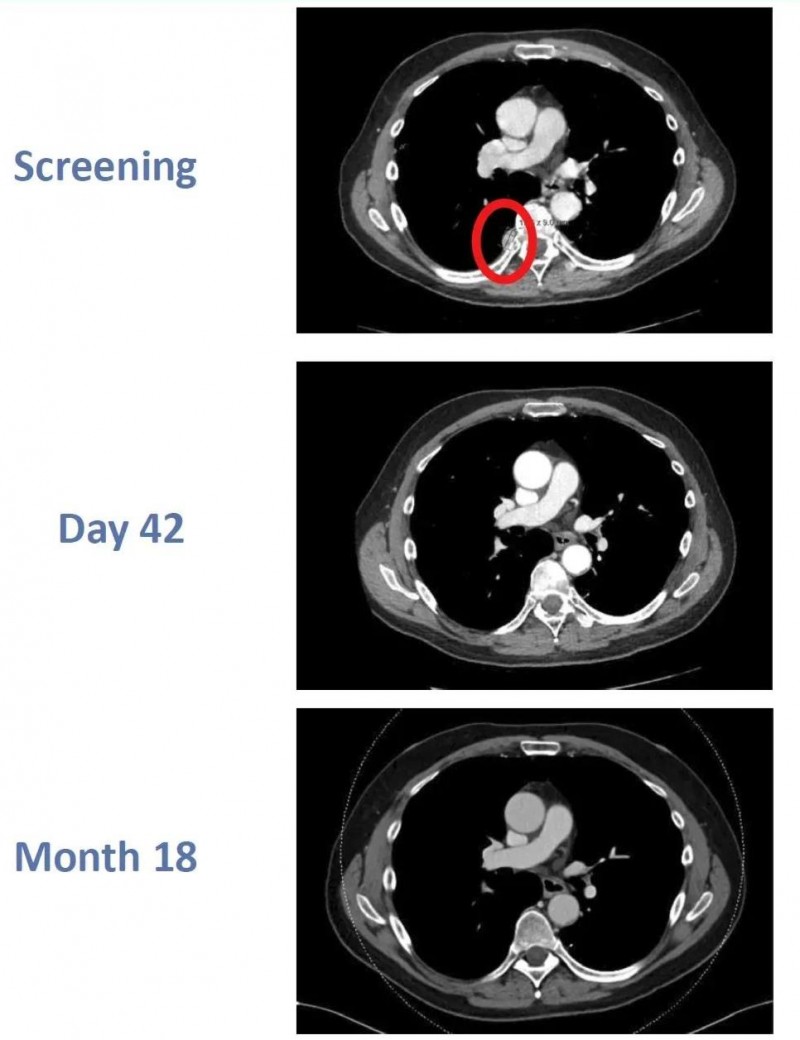

CTX130亮相2022年SITC大会,完全缓解(CR)持续18个月

2022年第37届癌症免疫治疗学会年会(SITC)上,也曾介绍过一个“经CTX130治疗后,获得完全缓解”的案例。本例患者为一位64岁透明细胞肾细胞癌男性,既往经卡博替尼、阿替珠单抗治疗后复发,出现胸膜及肺部转移灶。在入组接受CTX130治疗肾细胞癌的1期临床试验(NCT04438083)后,结果显示:

该患者在治疗后先获得了部分缓解(PR);在治疗第3个月时,居然达到了完全缓解(CR),而且完全缓解状态持续了18个月!

图2 患者在CTX130治疗前、治疗第42天、治疗第18个月时的影像学变化